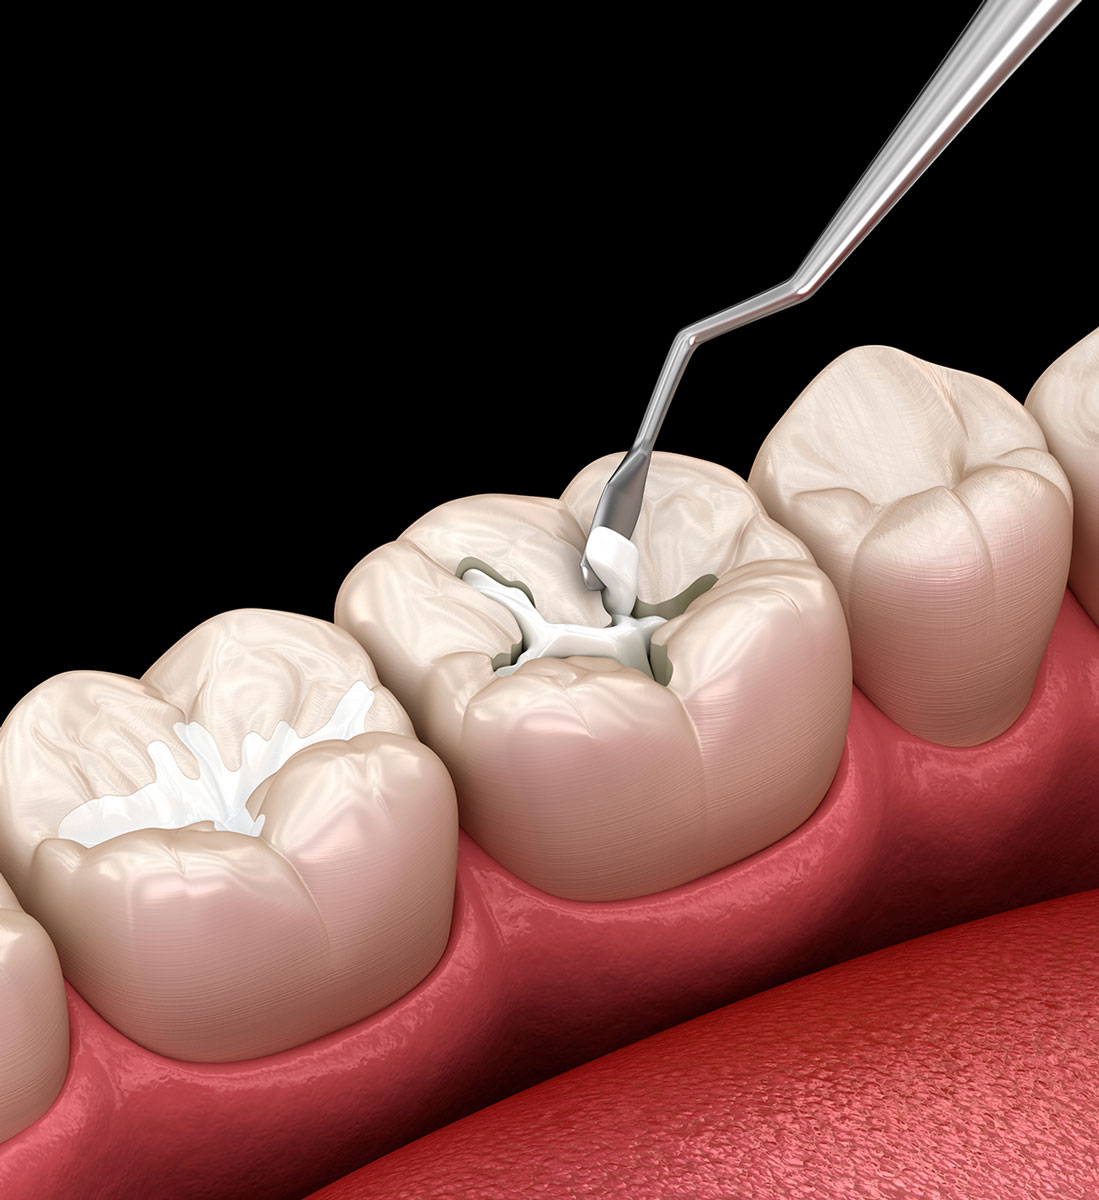

Odontoiatria Conservativa

In caso di denti spezzati, gravemente traumatizzati o devitalizzati, provvediamo immediatamente alla loro ricostruzione. La prassi prevede l’applicazione di tecniche differenti in base alla porzione da ricostruire. In ogni modo, ci affidiamo sempre a materiali altamente estetici e biocompatibili, come la ceramica.

Tecnica diretta: si applica immediatamente, soprattutto a seguito di una devitalizzazione, inserendo nella cavità dentale trattata un materiale riempitivo allo stato plastico che, poi, viene fissato in maniera indolore grazie all’ausilio di una lampada polimerizzante.

Tecnica indiretta: si applica quando la parte del dente rimossa è molto estesa e, per questo, richiede un restauro più complesso, come l’intarsio o la corona, che per essere realizzato può richiedere una seconda seduta.